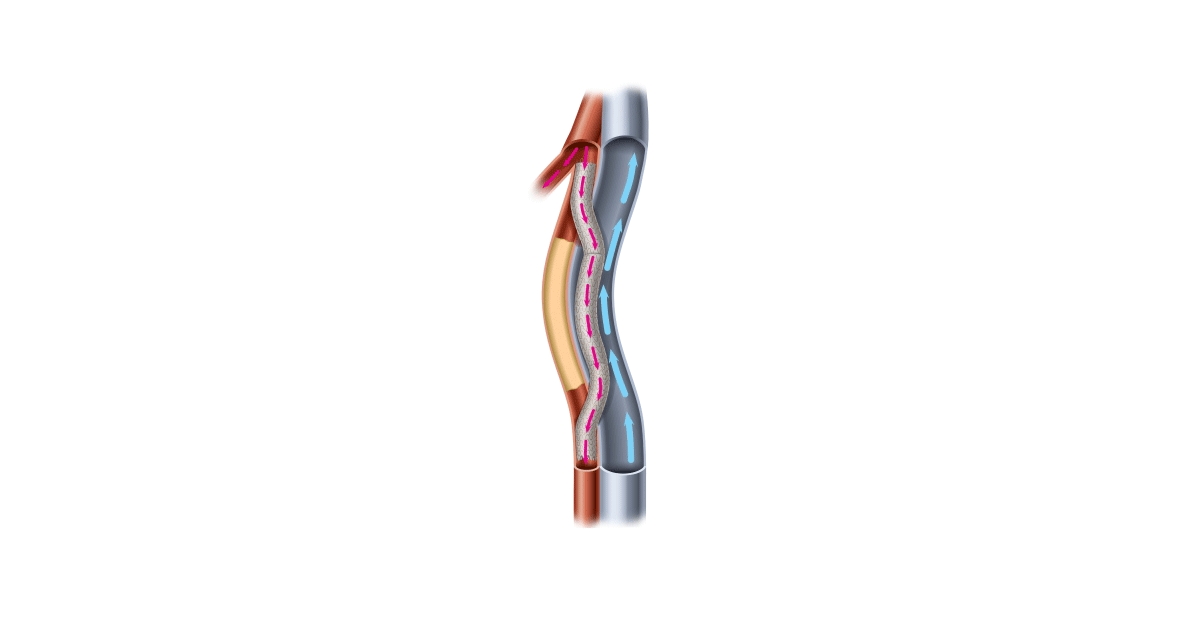

PQ Bypass gets FDA breakthrough device status for Detour System

PQ Bypass Announces CE Mark for DETOUR Percutaneous Bypass Technologies

PQ Bypass study meets safety efficacy endpoints MassDevice

PQ Bypass Incorporated docx 1 PQ Bypass Incorporated Performance

PQ Bypass Receives FDA Breakthrough Device Designation for the World

PQ Bypass Receives FDA Breakthrough Device Designation for the World

PQ Bypass Announces 60 Million Financing to Advance New Therapeutic

PQ Bypass Earns Frost amp Sullivan s European Technology Innovation Award